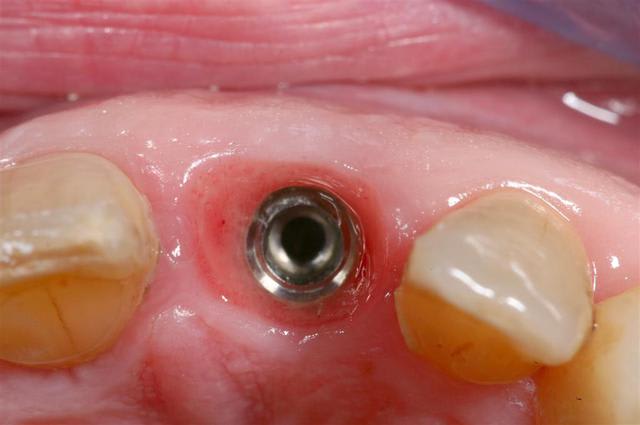

c'est tout simplement un faux moignon "droit" en titane idi

ils ont tous ce petit trou que j'utilise parfois pour l'enlever, lors des essais

Quel que soit le diamètre de 2,8 à 3,7 le col fait 4mm, cela simplifie la prothèse (peut être trop)

L'axe est effectivement un peu vestibulaire

photo d'un faux moignon droit